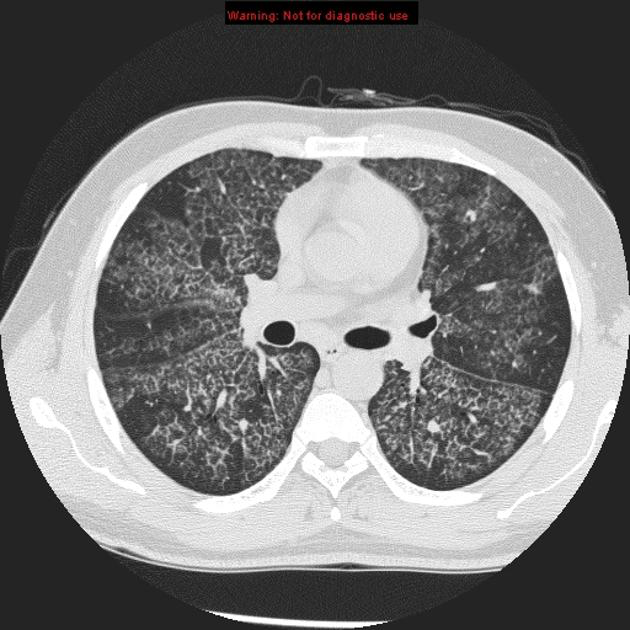

b) Crazy paving with septal thickening and GGO

What are the DDx for crazy paving? (5) ie septal thickening and GG